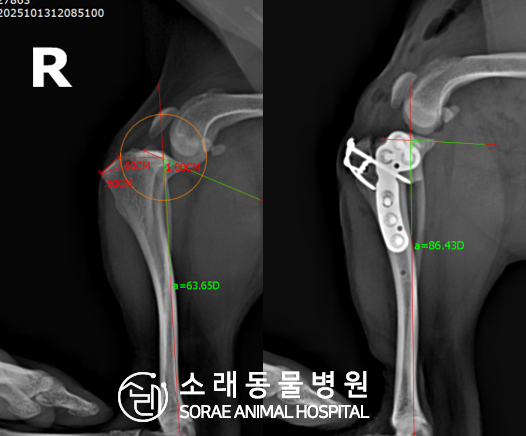

계산식으로 사전에 계획해두었던 플랜에 따라 경골을 절제하고

플레이트와 스크류를 사용하여 임플란트를 적용해 주었습니다.

반대 방향으로 밀려나 어긋나있던 대퇴골과 정강이가

제 자리를 찾으면서 무릎의 각도가 교정된 것을 확인할 수 있습니다